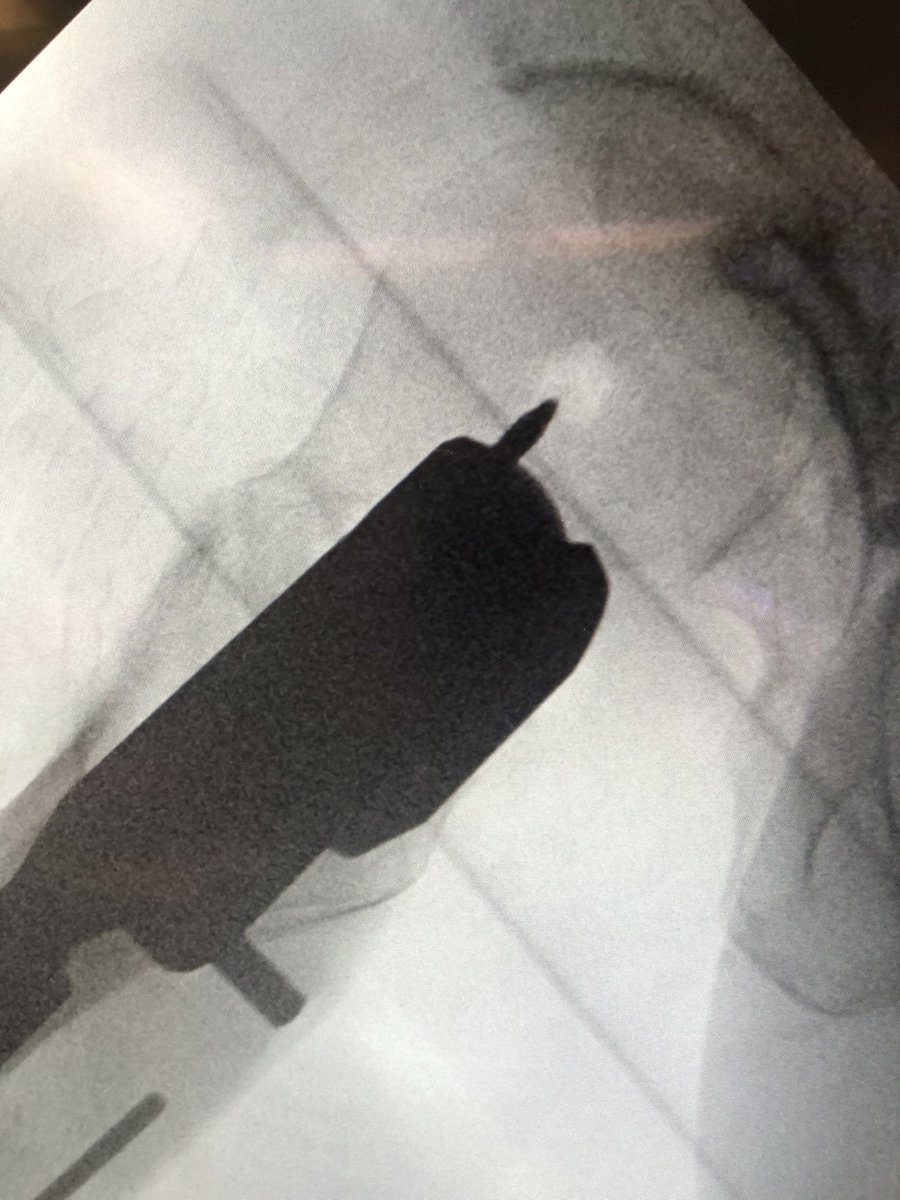

[10/18] At least in Synthes set they have long knife I call Big Bird. You can stick it through sleeve holes to get soft tissue trajectory right away instead of moving jig to use regular knife (sometimes you’ll still need it anyway, as excursion of Big Bird not always extensive).

[11/18] I bring wire up to about blue level (I also like to stay inferior, yellow) in order to see it on lateral. Be sure to remove impactor (metal) otherwise will get in way of visual. If I need to change adjustment on lateral, I drill in reverse & redirect wire also in reverse.

[12/18] To see head well, the c-arm has to be sufficiently “wagged” proximally (yellow). Usually that solves most of my problems with lateral. My angle is about 75 deg from vertical in the other plane, to make up for the usual 15 degrees of anteversion (not quite a full lateral).